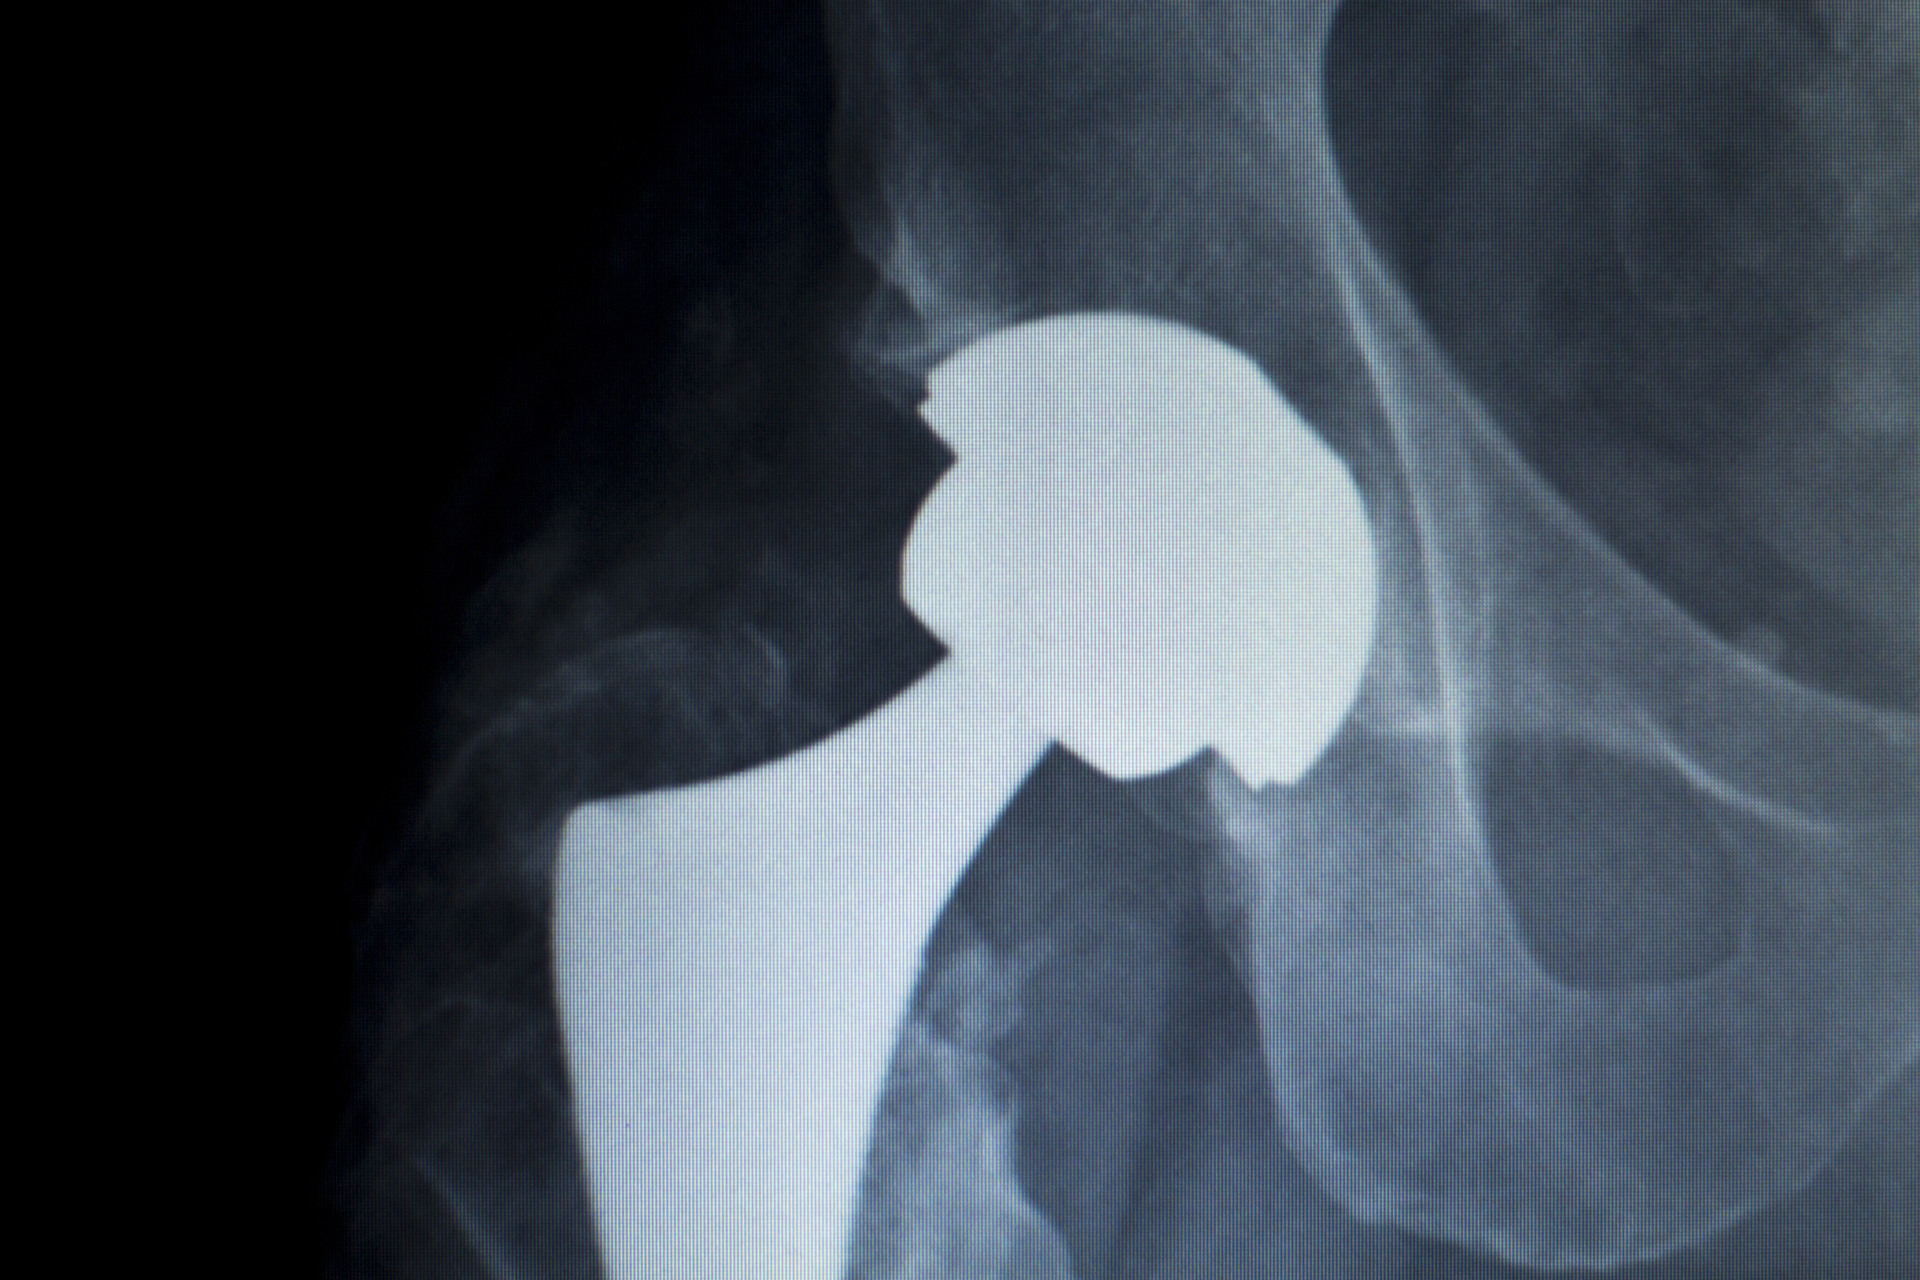

In 2025, it will become mandatory for hospitals under the Hospital Inpatient Quality Reporting (IQR) program to collect and report patient-reported outcomes for at least half of eligible total hip/total knee replacement patients. Healthcare Innovation recently sat down with 13-hospital Geisinger Health System’s Michael Suk, M.D., J.D., M.P.H., M.B.A., and Bronwyn Spira, CEO and co-founder of Force Therapeutics, a digital care management platform for musculoskeletal care, to discuss the implications of these changes.

Patients included in the report underwent a wide range of hip, knee, shoulder, and spine procedures, providing thousands of data points to evaluate utilization, patient experience, and outcomes based on standard scoring tools for clinical benefit, function, disability, mental health, and well-being.